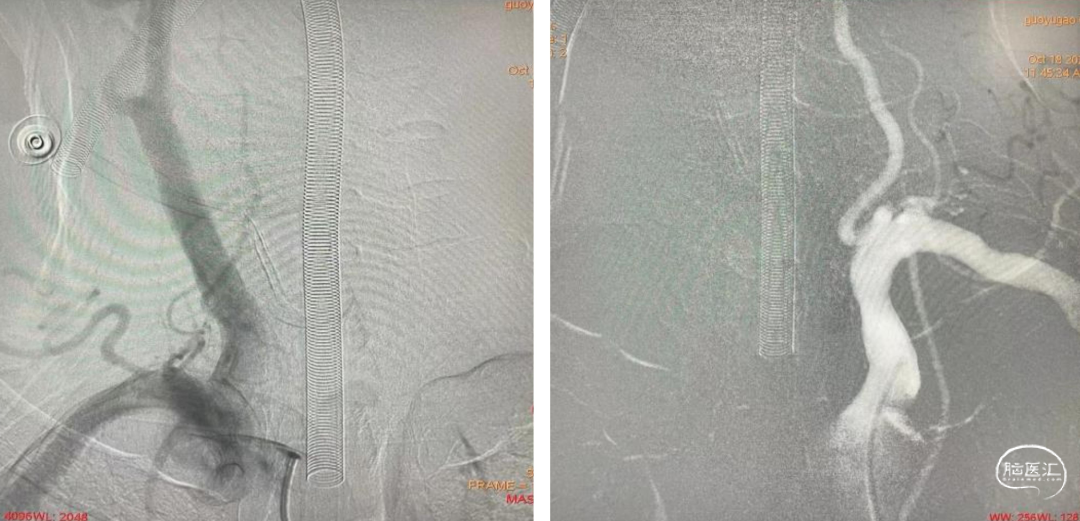

术前造影示:右侧椎动脉纤细,左侧椎动脉优势,起始部走形迂曲。

5F 125cm多功能造影管、6F 115cm 通桥银蛇®颅内支撑导管同轴顺利通过左侧椎动脉起始部走形迂曲血管,到达椎动脉V4段,微导管造影确定真腔内。

球囊准确对位后扩张狭窄处。